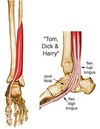

What muscles make up the (i) Anterior Compartment (ii) Lateral Compartment of the leg? What nerves supply the (a) Anterior Compartment (b) Lateral Compartment of the leg?

(i) Tibialis anterior Extensor hallucis longus Extensor digitorum longus Peroneus(fibularis) tertius (ii) Peroneus (fibularis) brevis Peroneus (fibularis) longus

(a) Deep fibular nerve (L4, L5)

(b) Superficial fibular nerve (L5, S1, S2)

What muscles make up the (i) Posterior Superifical Compartment (ii) Posterior Deep Compartment of the leg? What is their common innervation?

(i) Gastrocnemius

Soleus

Planatris

(ii) Popliteus

Flexor Hallucis Longus

Flexor Digitorum Longus

Tibialis Posterior

TIBIAL NERVE (L4 - S3)